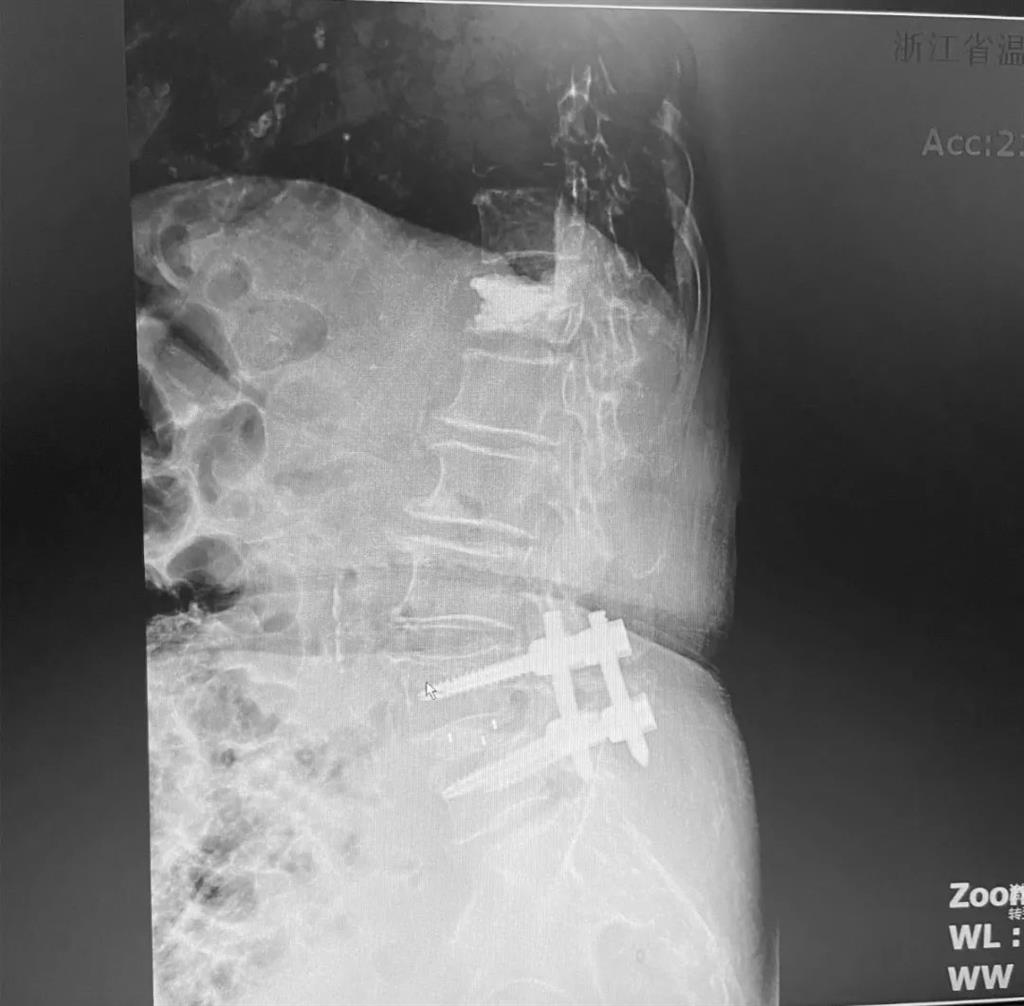

據(jù)了解,脊柱內(nèi)鏡下腰椎融合術(shù)只需要打幾個(gè)“鑰匙孔”即可完成。聽(tīng)起來(lái)是不是很簡(jiǎn)單?在脊柱內(nèi)鏡下,劉丹主任先后為患者進(jìn)行了椎管減壓、椎間盤(pán)摘除,再實(shí)施椎弓根螺釘放置、椎體植骨融合內(nèi)固定,一系列步驟有條不紊。

劉丹主任表示,傳統(tǒng)手術(shù)需要廣泛剝離脊椎兩側(cè)的肌肉,術(shù)后容易產(chǎn)生疤痕、肌肉萎縮、腰部疼痛等;術(shù)中出血多,往往需要額外輸血,另外創(chuàng)傷大的同時(shí)也容易破壞脊椎的正常結(jié)構(gòu),對(duì)于老年人、體弱的人群來(lái)講,恢復(fù)期長(zhǎng)、風(fēng)險(xiǎn)多。

而脊柱內(nèi)鏡下腰椎融合術(shù),作為目前國(guó)內(nèi)脊柱微創(chuàng)領(lǐng)域大力發(fā)展的新技術(shù),徹底改變了傳統(tǒng)開(kāi)刀椎板切除椎間植骨融合內(nèi)固定的大創(chuàng)傷現(xiàn)狀,可以在較大程度上減少對(duì)脊柱后方穩(wěn)定結(jié)構(gòu)的破壞,創(chuàng)傷小,出血少,術(shù)后恢復(fù)快。

非常適用于體質(zhì)較差不能耐受開(kāi)放手術(shù)的老年患者,且手術(shù)全程均在內(nèi)鏡監(jiān)測(cè)下進(jìn)行,能夠最大程度地避免硬膜囊和神經(jīng)根損傷,手術(shù)安全性更高。